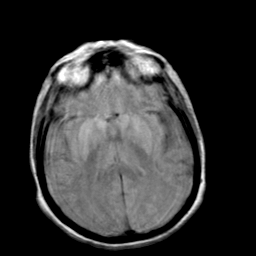

Creutzfeld-Jakob disease: proton density-weighted MR -- Slice #13

[Home][Help][Clinical] Slice 13